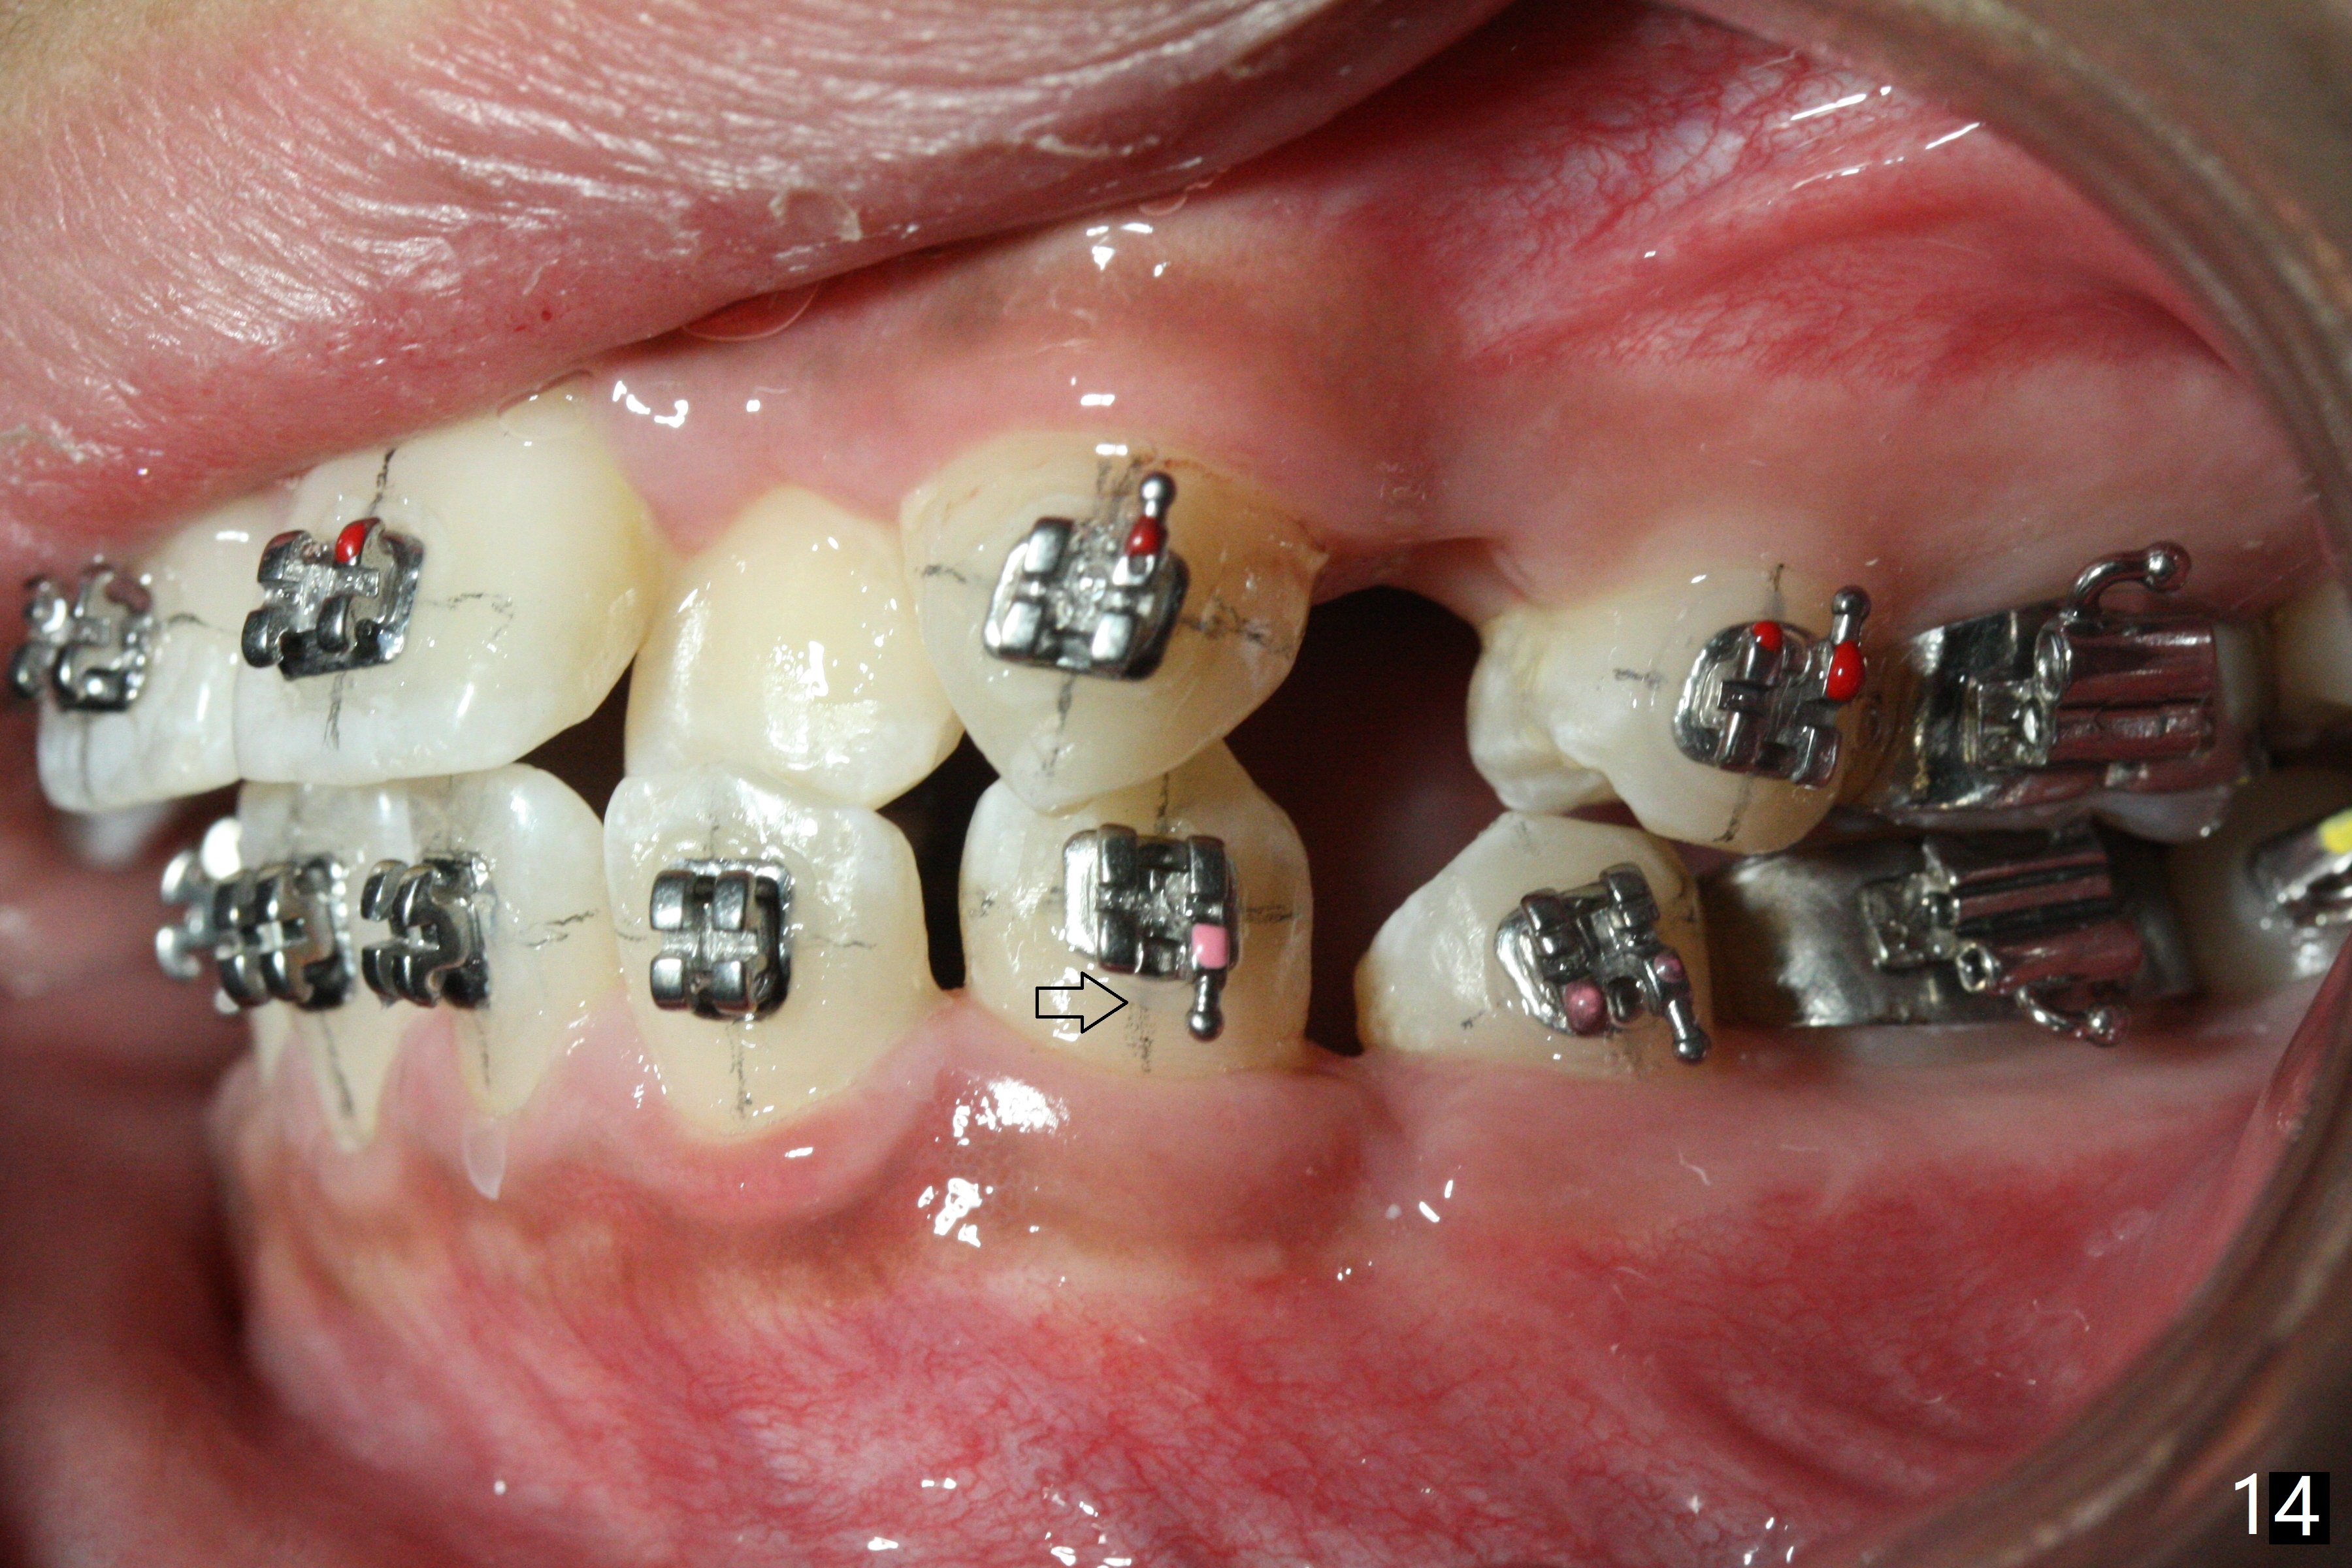

In fact, automatic shifting is striking.  For example, UR5 lingualization (Fig.12 arrow) makes it easy to insert 12 niti wire.  Distalization of the lower bicuspids and canine is more obvious (Fig.13,14 arrows) than the upper counterparts.  Because of incomplete eruption, it is difficult to band L7s; instead brackets are placed (Fig.15-17).  The purpose of LR one is to facilitate LR6 buccalization (Fig.15,16), whereas LL one to correct rotation of itself (Fig.17).